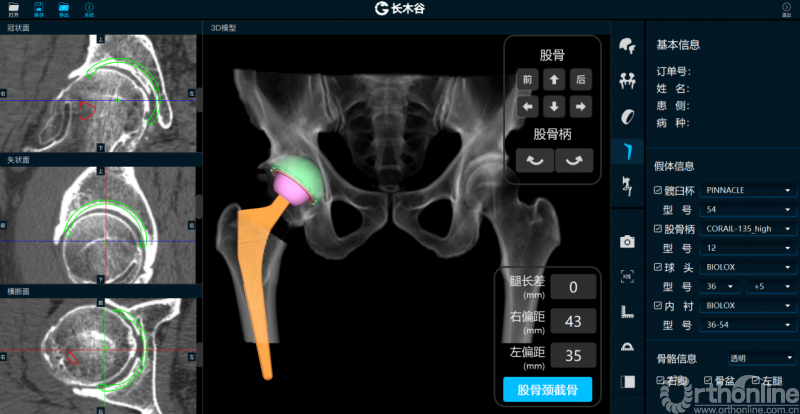

AI HIP系统对患者术前偏距与腿长差进行智能测量与评估

而后,由人工智能判断患者双侧腿长差及股骨偏心距大小,如图可见,由于长期受到的髋关节撞击征影响,该患者术前腿长差为2mm,右侧股骨偏心距为43mm,明显大于左侧股骨偏心距35mm。

最后,AI HIP系统根据患侧股骨颈干角、偏心距偏大的特殊情况,智能选择使用高偏高颈干角假体,对下肢等长和等偏心距重建做出了精准设计。根据系统预测结果,术中使用54mm Pinnalce髋臼杯、12号CORAIL高偏股骨柄、36mm 陶瓷股骨头、小转子上23mm截骨,实现髋关节的个体化、精准化重建。